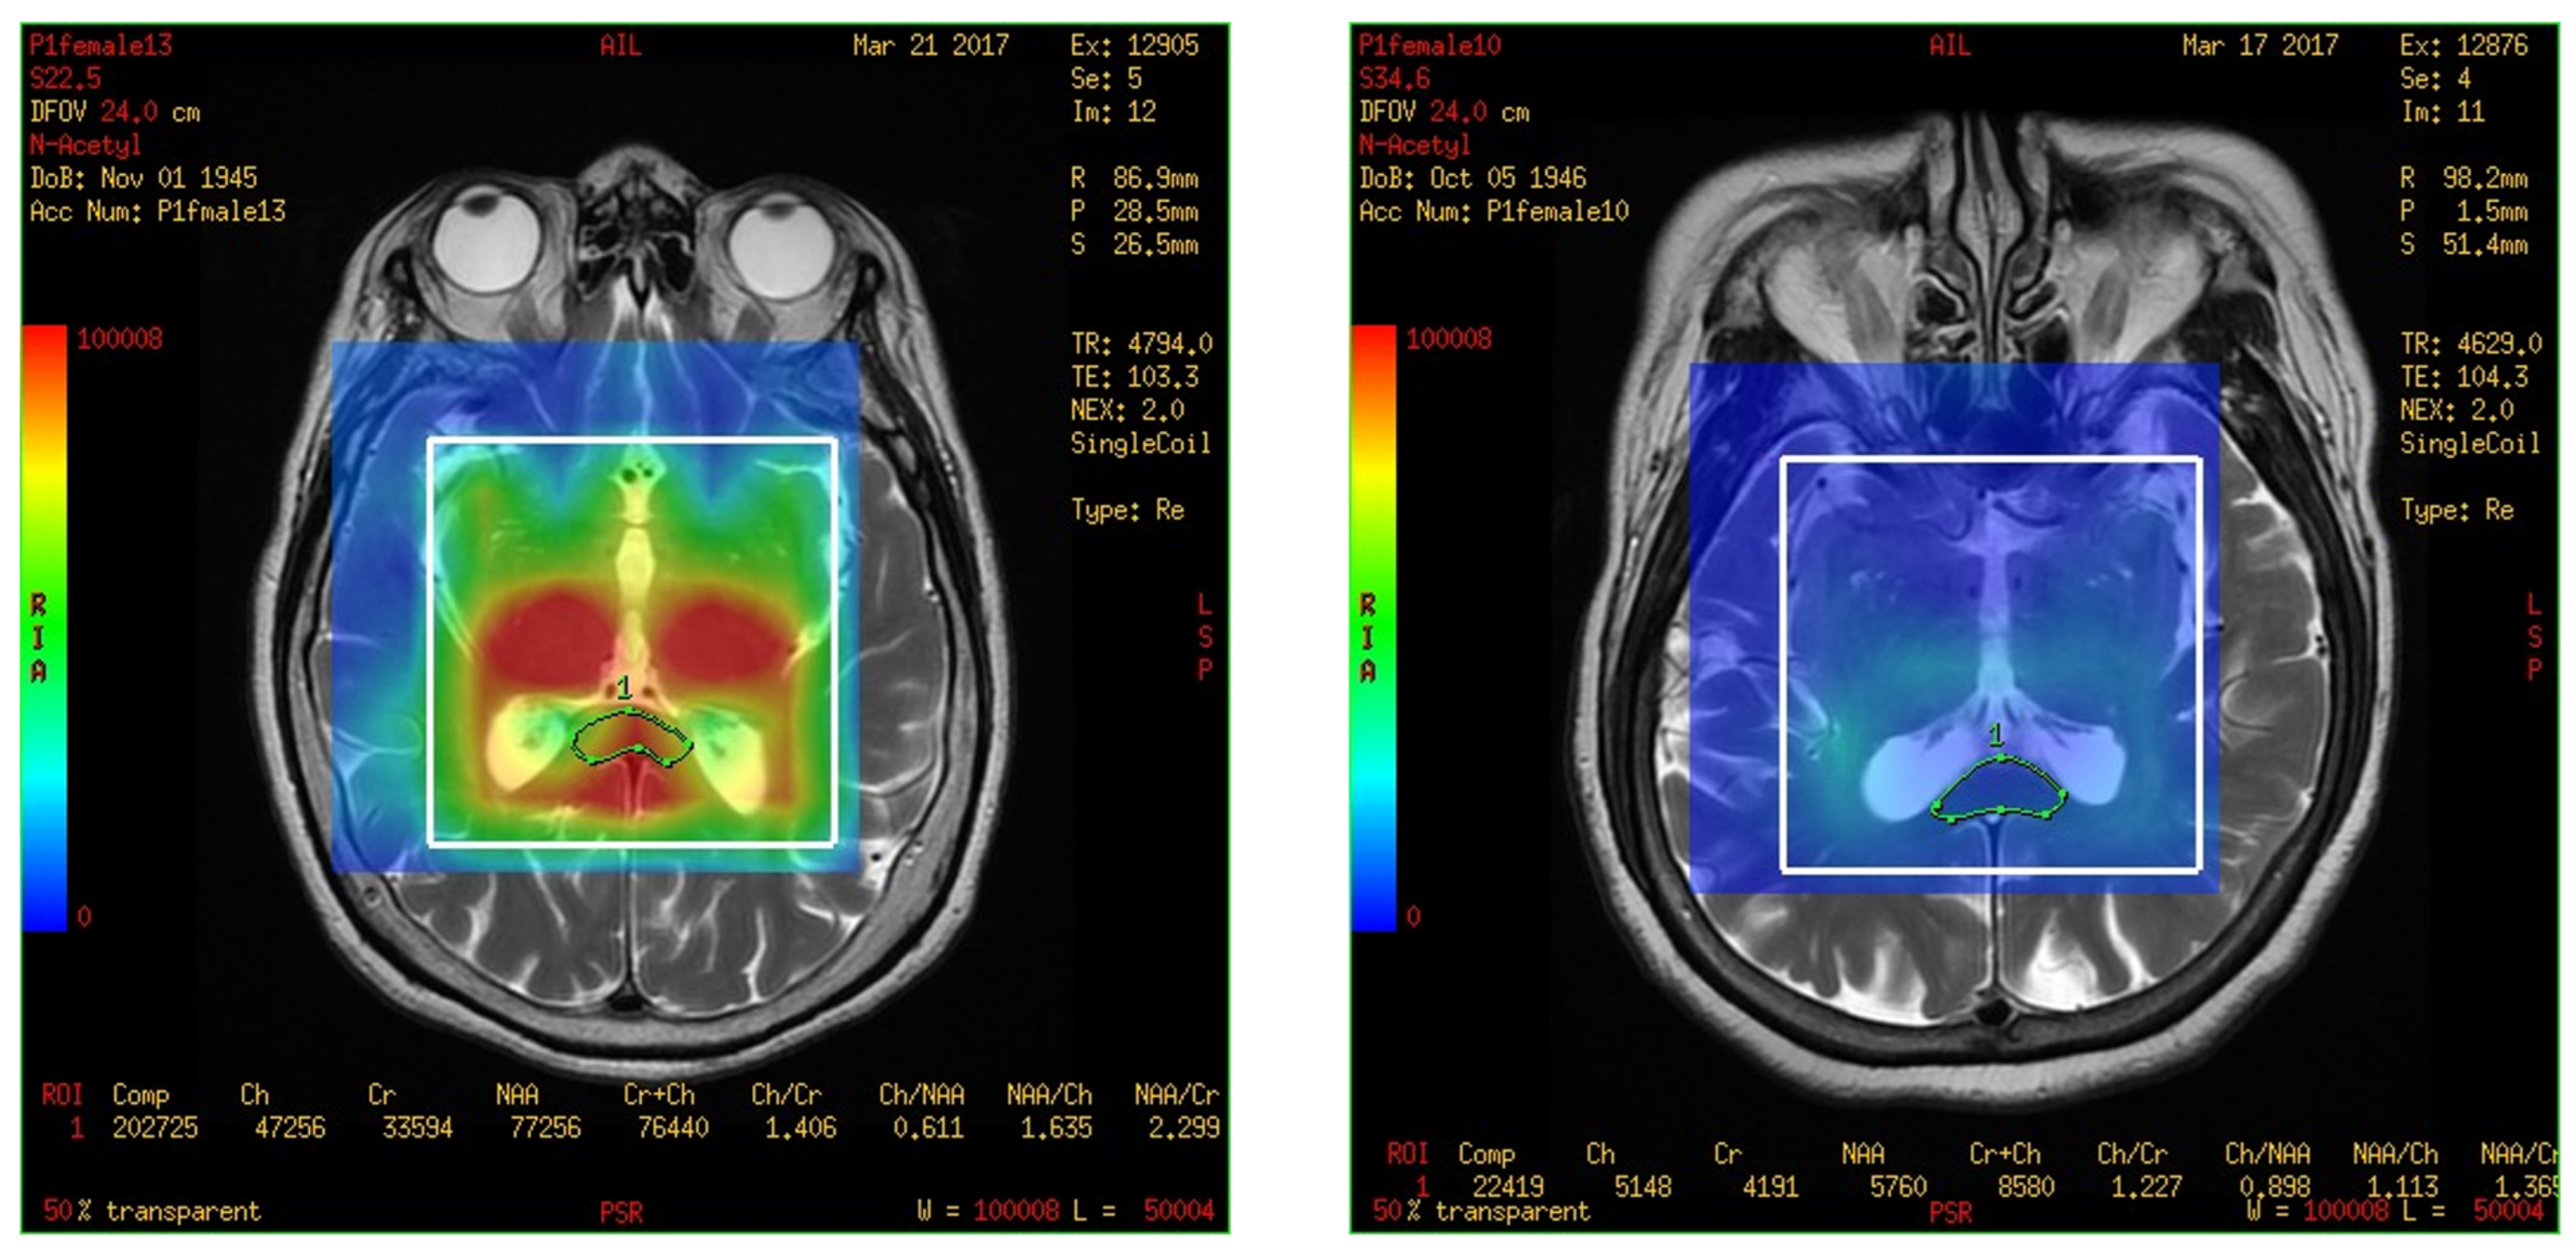

In this study, a medical 1.5 T MRI machine (GE Signa HDxt Medical Systems, Waukesha, WI, USA) and a standard head coil (Head Coil) in Camillians Saint Mary’s Hospital Luodong were used to receive signals from brain images of MRI T1 and T2 sequences, and 1H-MRS with 3D-CSI (echo time (TE) 144 ms, repetition time (TR) 1000 ms) for all participants. The range of chemical shift was set from 0 to 4 ppm, as this could include the signal of most metabolites in the brain, and the volume of each voxel was set at approximately 1–1.5 square centimeters. The measurements were performed as follows: First, brain images of T1 and T2 sequence with 3-Plane localization (sagittal, axial, and coronal planes) were obtained to locate the hippocampus and corpus callosum in the brain. Second, the three-dimensional space of the hippocampus and corpus callosum was manually marked and chosen on the image by a technician. Subsequently, the three-dimensional space of the hippocampus was divided into the total (bilateral), right, and left hippocampi. Third, the MRS with 3D-CSI was performed in the chosen location of the hippocampus (Figure 1) and corpus callosum (Figure 2). The signal intensities of choline (Cho), N-acetyl aspartate (NAA), creatine (Cr), and myo-inositol (MI) in the total (bilateral), right, and left hippocampi and the corpus callosum were measured and recorded in arbitrary units and used for statistical analysis.

Figure 1. Magnetic resonance spectroscopy with three-dimensional chemical shift images in the chosen location of the left and right hippocampi (purple markup). The signal intensities of metabolites were measured and recorded.